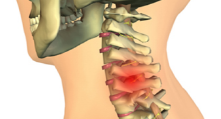

경추신경이 압박되면 신경의 전기 신호가 잘 전달되지 않아 저림 현상이 발생할 수 있습니다. 이는 손가락이나 팔, 어깨, 목 등 신체의 다른 부위에서도 느껴질 수 있습니다. 또한, 신경의 손상이 심한 경우, 팔과 다리를 움직이는 것이 어렵게 될 수 있습니다.

이러한 저림현상은 일상생활에서 큰 불편함을 초래할 수 있으며, 목디스크 환자는 적극적인 치료가 필요합니다.